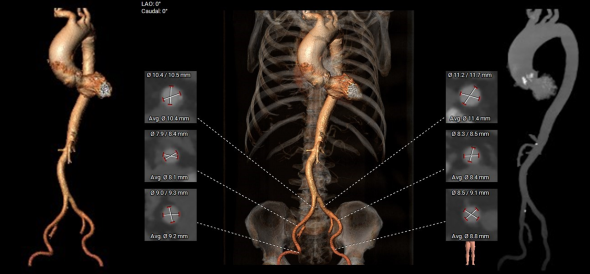

主动脉根部测量

CT特点:Type 0型二叶式主动脉瓣,左右冠不同窦,瓣叶中重度钙化伴增生肥厚,钙化呈偏心性分布;左右冠开口高度可,无冗长瓣叶;近横位心,心室壁肥厚。